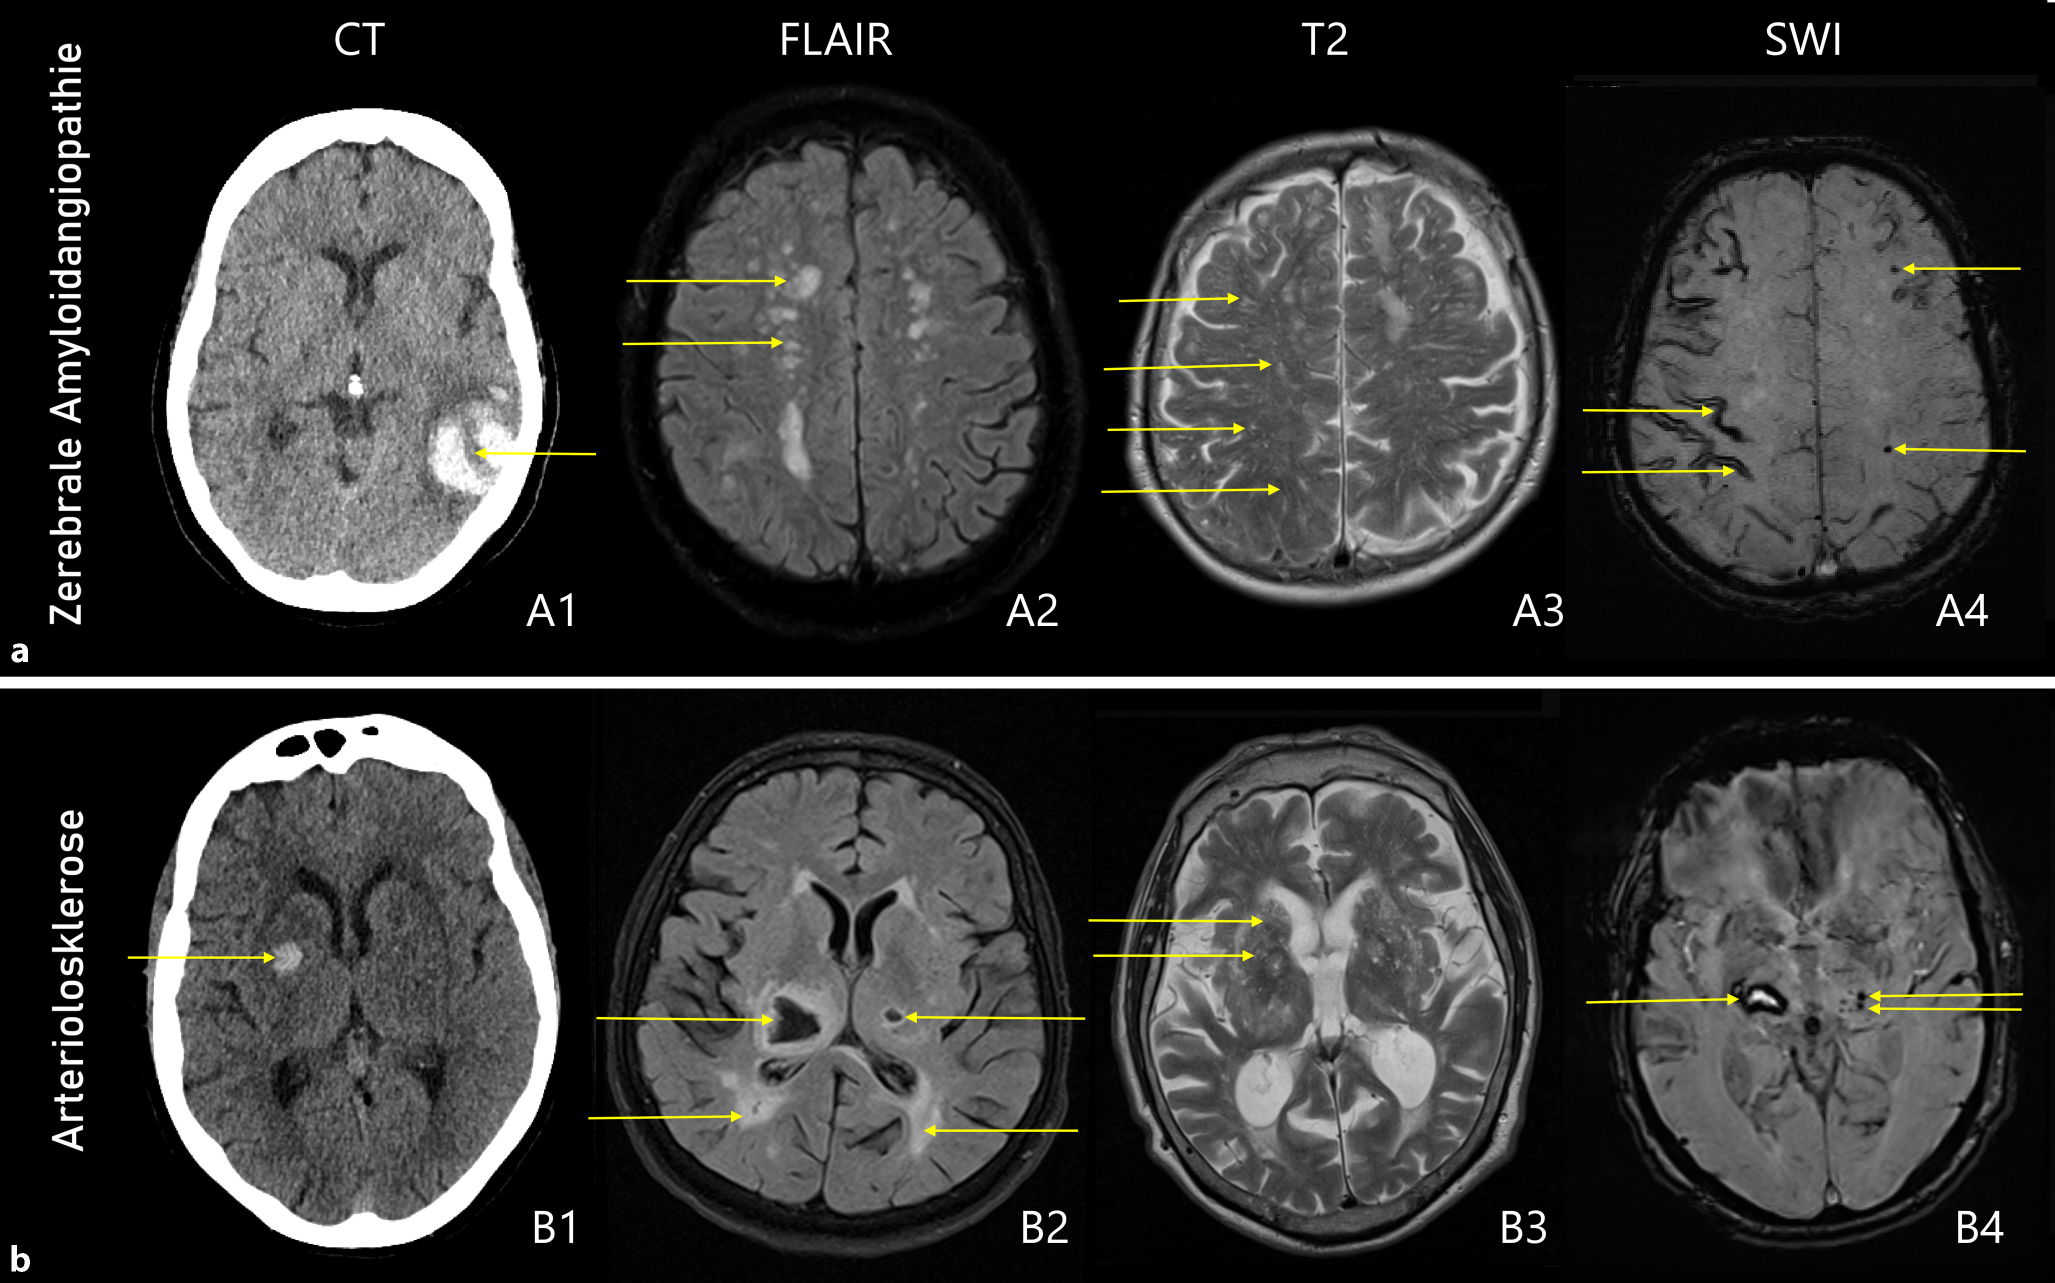

Bei der Arteriolosklerose (Arteriopathie der tiefen Perforationen, „hypertensive“ Mikroangiopathie) zeigen sich in der MRT typische Veränderungen dieser Erkrankung: Marklagerhyperintensitäten („white matter hyperintensities“), Lakunen, subkortikale Mikroblutungen und erweiterte perivaskuläre Räume in den Basalganglien (siehe Abb. 1a). Bei Fortschreiten der Arteriolosklerose treten häufig auch lobäre Mikroblutungen und teils auch lobäre ICB auf, weshalb die Arteriolosklerose auch eine der wichtigsten Differenzialdiagnosen bei lobären ICB darstellt.

Abb. 1

Typische bildgebende Zeichen bei zerebraler Amyloidangiopathie: Lobäre ICB mit „finger-like projections“ (A1), Marklagerhyperintensitäten in einem „multispot pattern“ (A2), erweiterte perivaskuläre Räume im Centrum semiovale (A3), kortikale superfizielle Siderose und lobäre Mikroblutungen (A4). Arteriolosklerose: Tiefe ICB (B1), tiefe Lakunen und Marklagerhyperintensitäten (B2), erweiterte perivaskuläre Räume in den Basalganglien (B3), tiefe Mikroblutungen neben einer Thalamusblutung (B4). © S. Fandler-Höfler

Gezielte Behandlung und Sekundärprophylaxe

Bei Patient:innen mit CAA finden sich neben lobären ICB typischerweise lobäre Mikroblutungen, eine kortikale superfizielle Siderose oder sulkale Subarachnoidalblutungen (siehe Abb. 1b). Für die bildgebende Diagnose ist die aktuell überarbeitete Version der Boston-Kriterien hilfreich, welche für eine Diagnose einer „wahrscheinlichen CAA“ zwei hämorrhagische lobäre Veränderungen (siehe oben) oder eine hämorrhagische Veränderung plus ein „white matter feature“ (deutlich erweiterte perivaskuläre Räume im Centrum semiovale oder eine sogenannte „white matter hyperintensity“ „multispot pattern“) vorsehen. Ein Alter < 50 Jahren schließt die Diagnosestellung einer (sporadischen) CAA aus, ebenfalls schließen die Boston-Kriterien alle Patient:innen mit „tiefen“ (subkortikalen) hämorrhagischen Veränderungen (ICB, Mikroblutungen) von der Diagnose einer CAA aus.